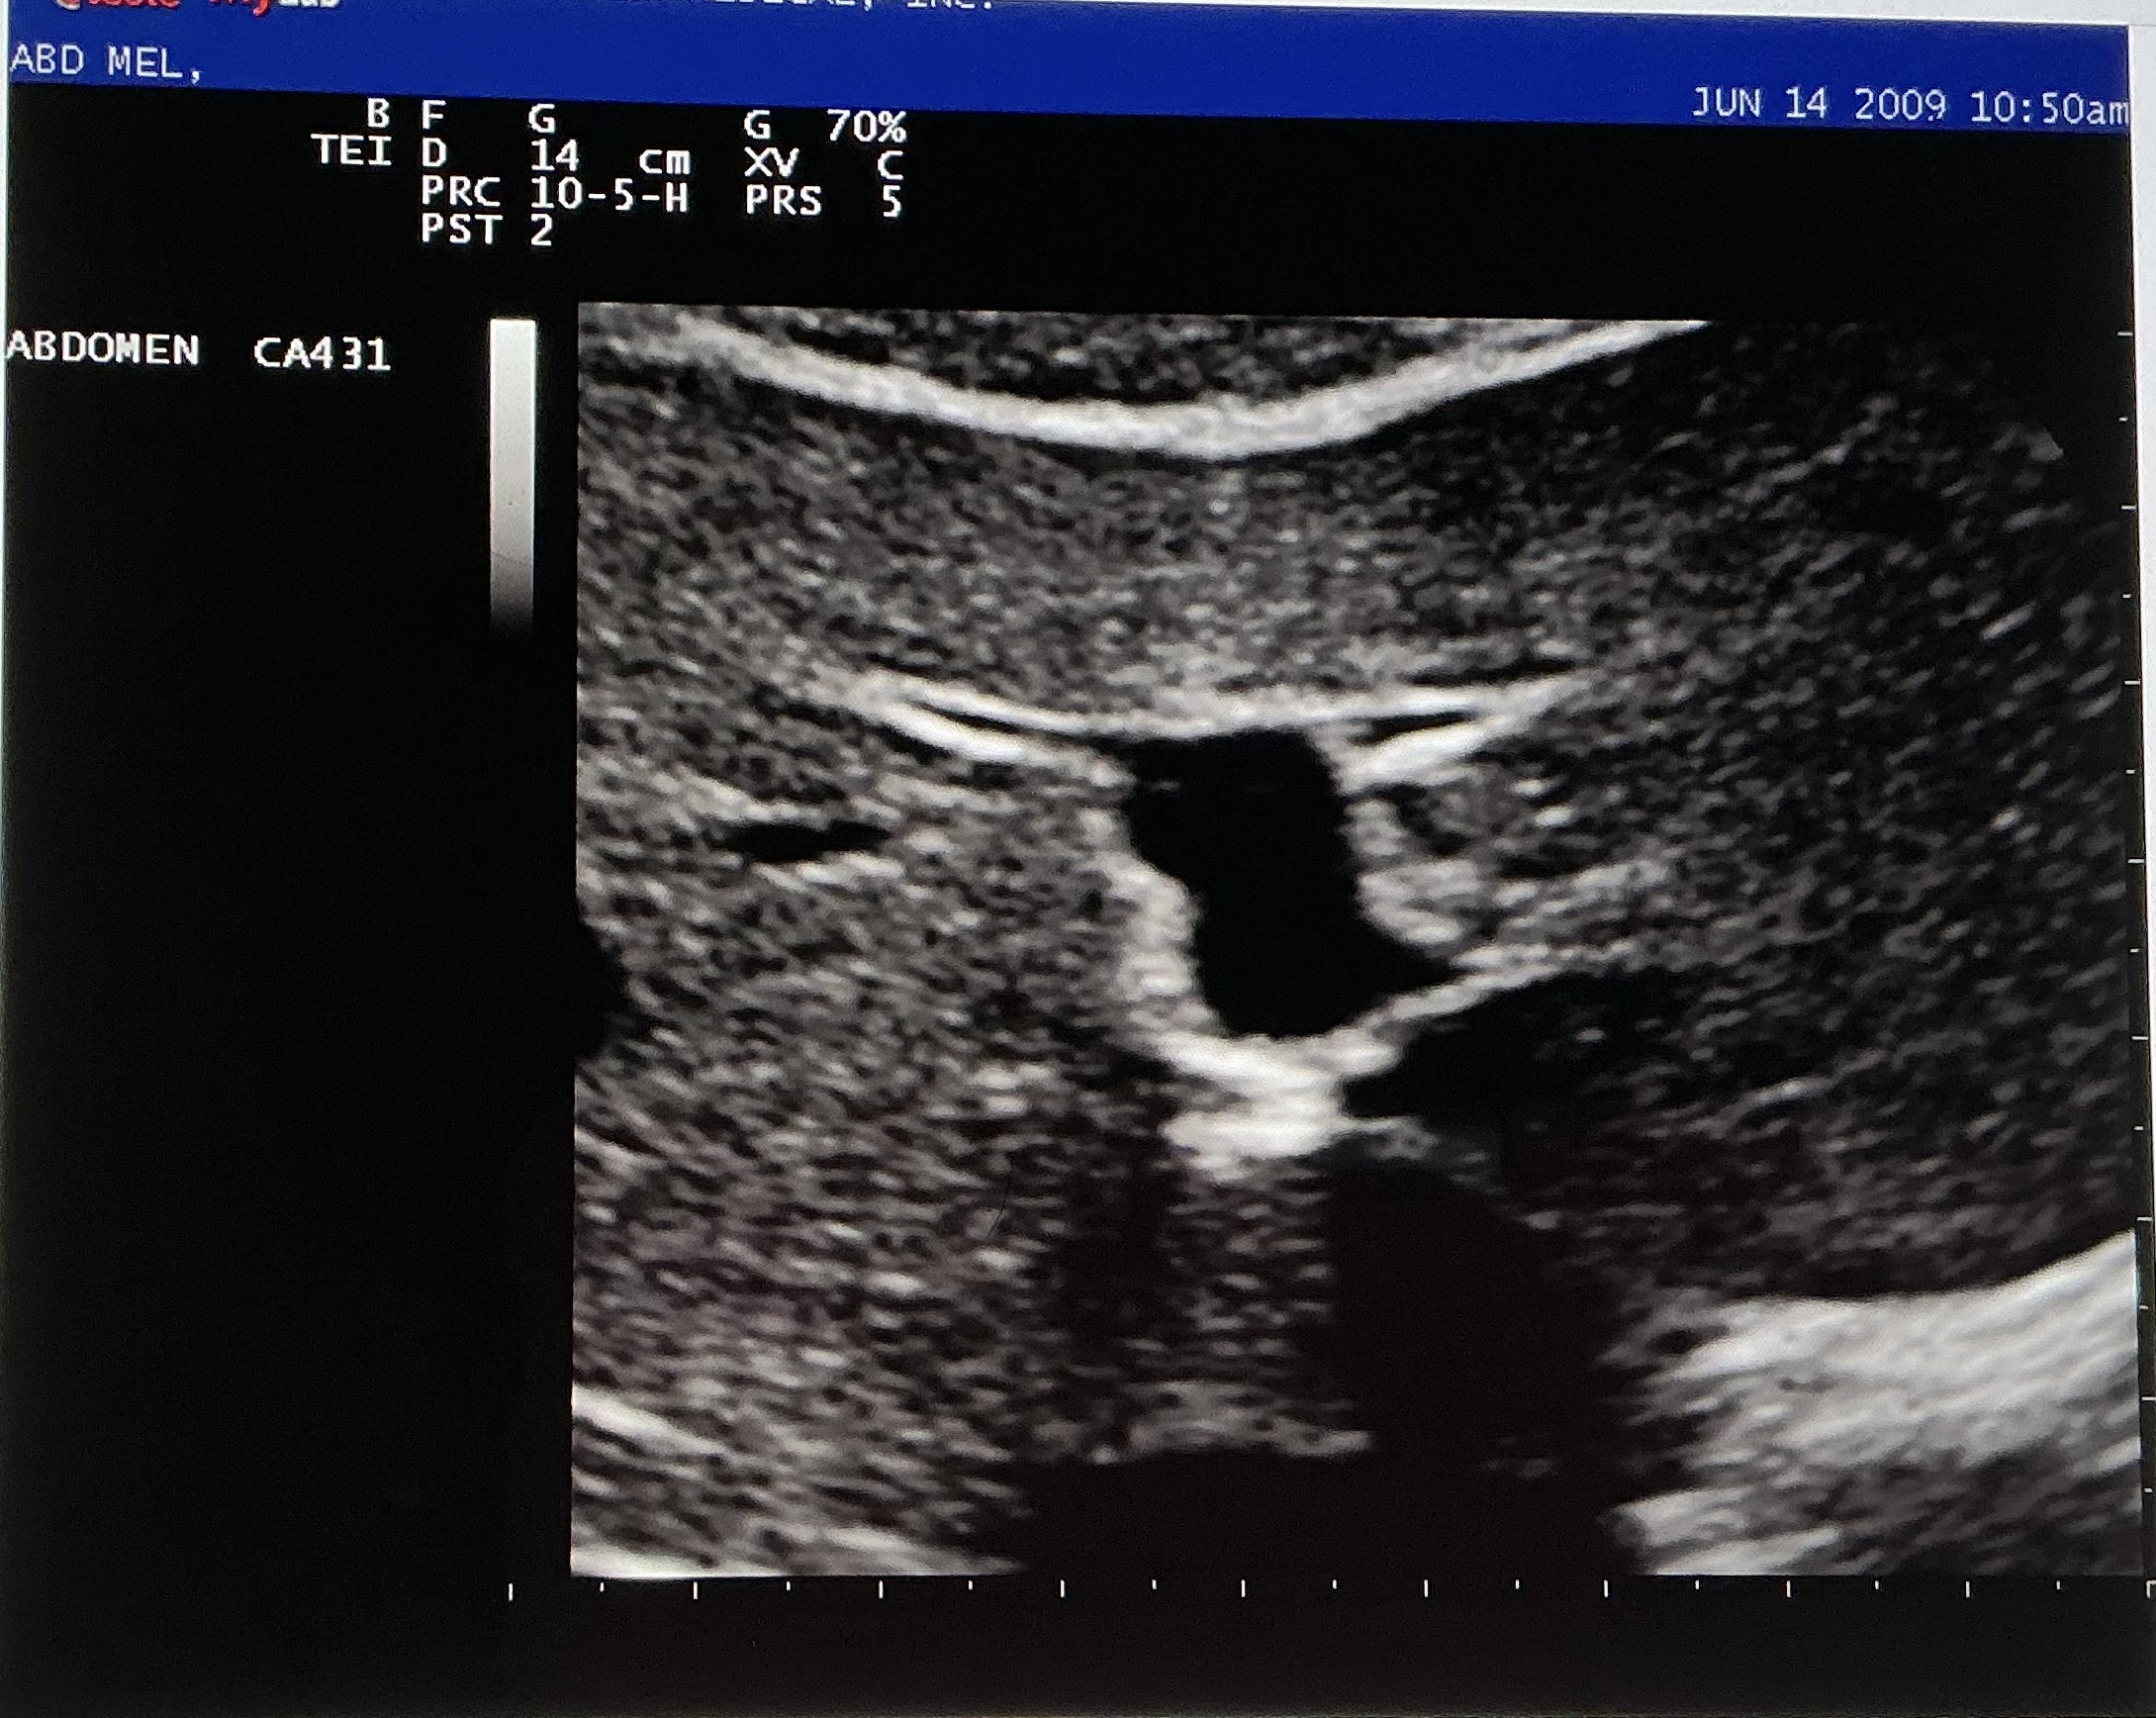

What branch of the MPV is shown in the image?

left

What are the names of the smaller branches of the vessel shown?

left medial and left lateral portal veins